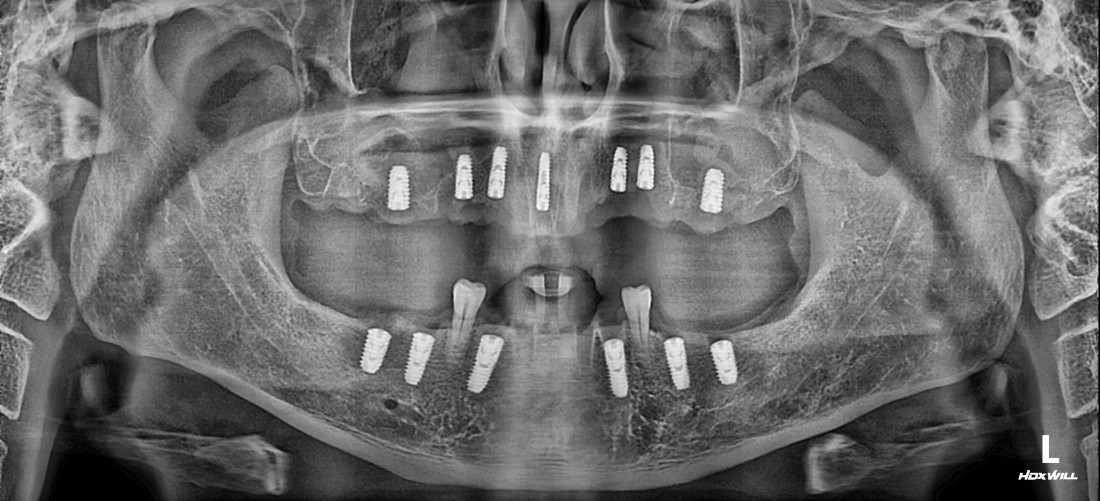

![]() | ![]() |

수완동 임플란트 치과에서는

디지털 가이드 임플란트를 통해

자동차가 네비게이션을 따라

정확한 목적지에 도착하듯,

가이드 임플란트를 제작하여

미리 컴퓨터로 모의시술을 진행하고

정확한 위치에 정확한 깊이로

임플란트를 식립하고 있습니다.